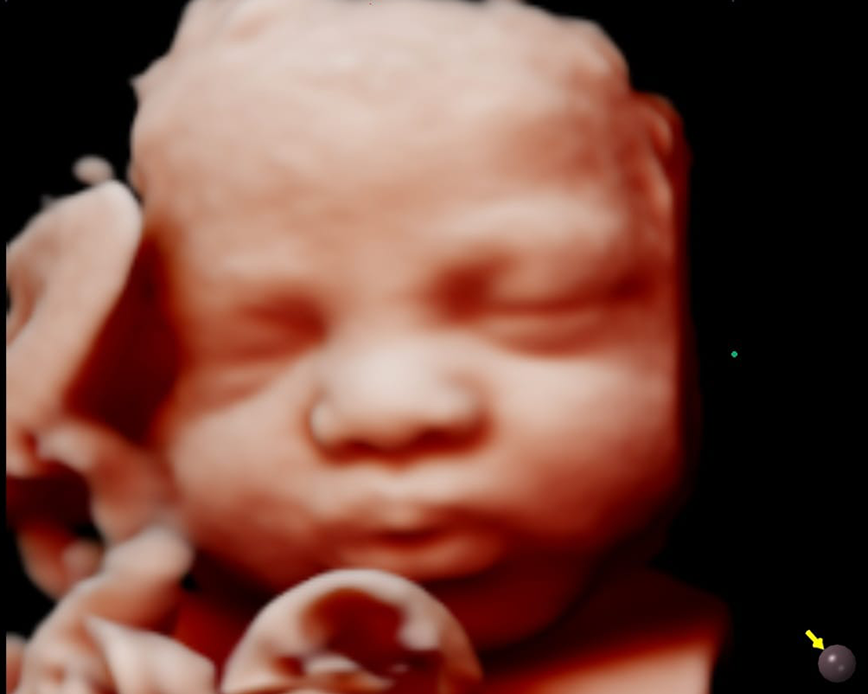

Con nuestra tecnología 5D y 6D de alta resolución, podrás ver la carita, las manos, los pies, la columna y el sexo de tu bebé con imágenes de alta calidad. Además, podrás apreciar los gestos de tu bebé en tiempo real. Esta ecografía también nos ayuda a detectar las malformaciones congénitas que pudiera tener el feto.